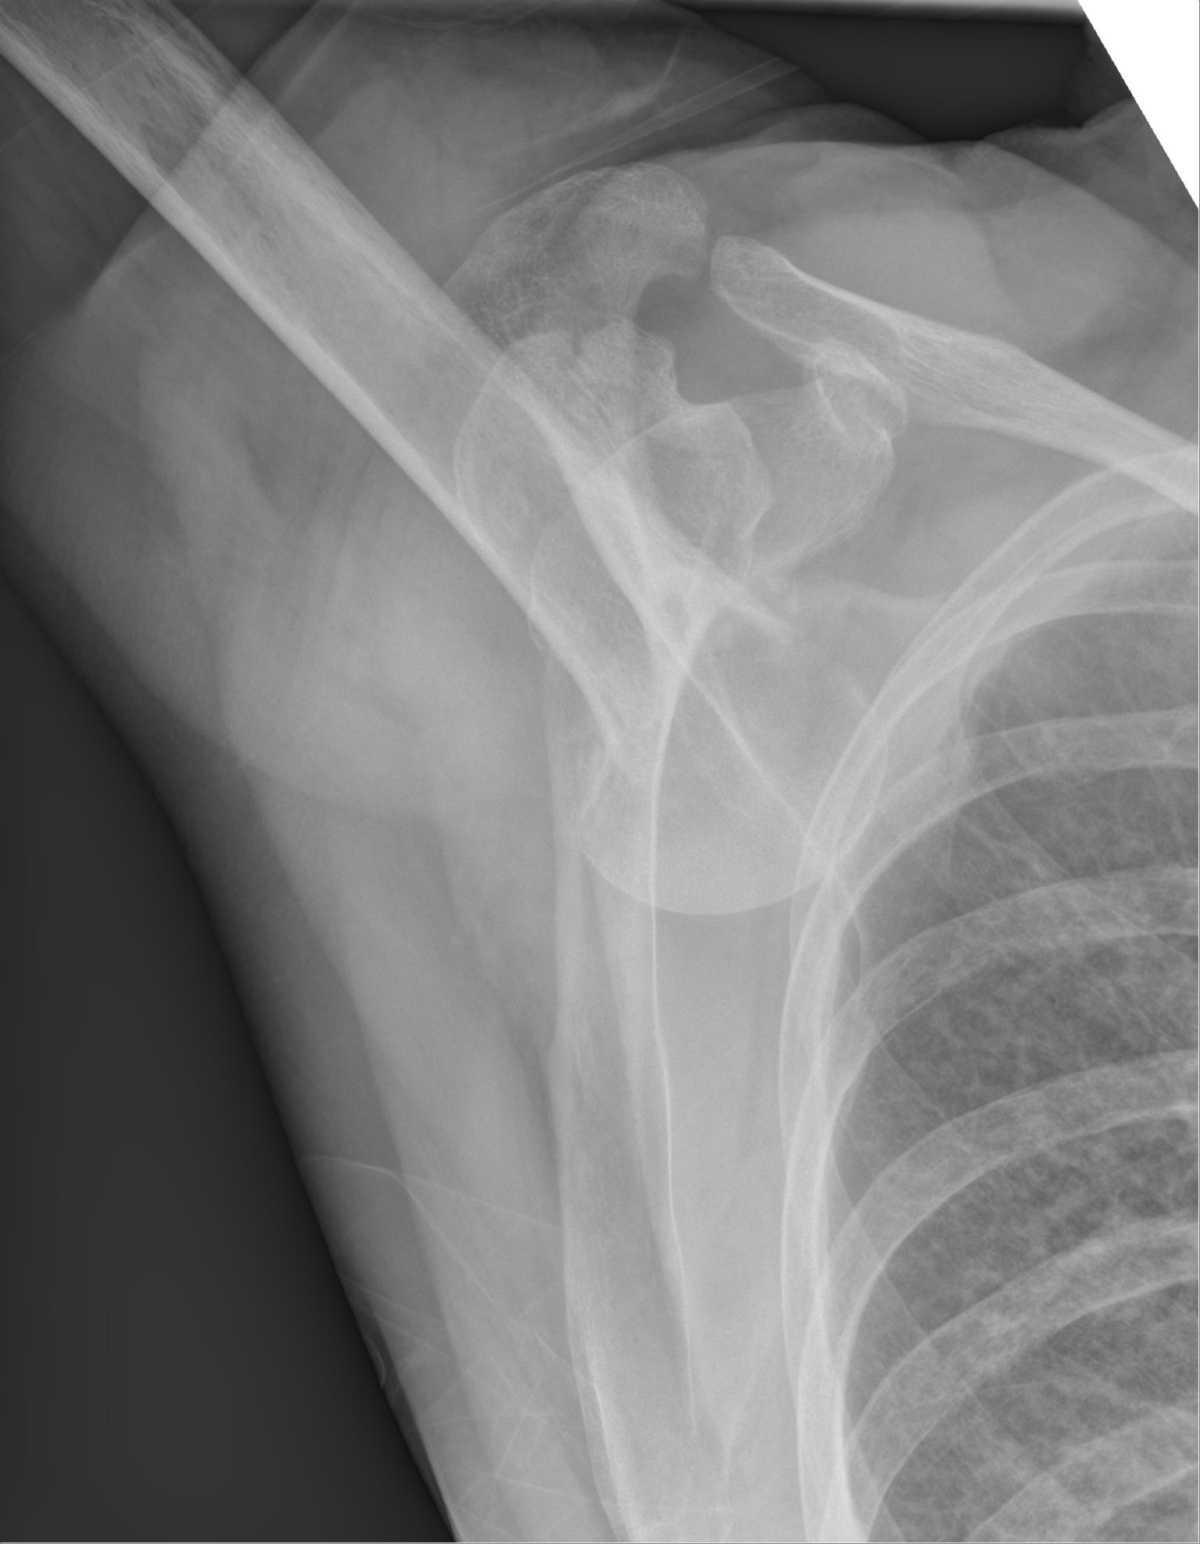

Aspect normal:

Matt A. Morgan, Radiopaedia.org. From the case rID: 85739